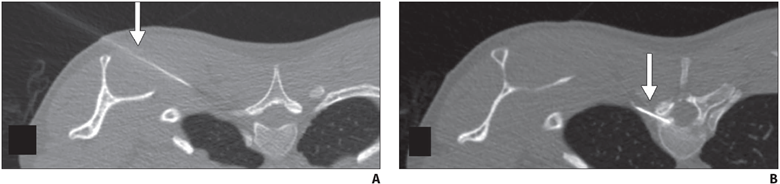

Dural Defects and Meningeal Diverticula

First-line treatment of dural defects and leaking meningeal diverticula is targeted epidural blood and/or fibrin glue patching. The epidural space can be accessed via dorsal interlaminar or transforaminal approaches depending on the type of leak. In dorsal interlaminar approaches, a loss of resistance technique using air can be performed to ideally position the needle in the epidural compartment, whereas in transforaminal approaches, epidural position can be confirmed with injection of a small amount (approximately 0.5 mL) of dilute iodinated contrast material to observe epidural spread of injectate. As many dural defects are ventral, far lateral transforaminal approaches can be used to attempt to access the ventral epidural space (Fig. 7).

Fig. 7—45-year-old man with orthostatic headaches and confirmed ventral dural defect at T1-2 level.

A and B, Sequential axial CT slices obtained during epidural blood patching show far lateral transmuscular approach using 15-cm spinal needle (arrow) to reach ventral epidural space at T1-2 level.